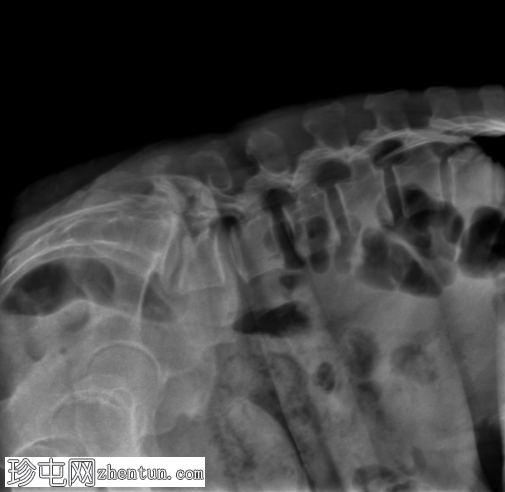

X光片

1.png

正面

L5-S1 椎体II度滑脱。

双侧椎间盘缺损。

L5-S1椎间盘间隙缺失,伴有退行性病变。